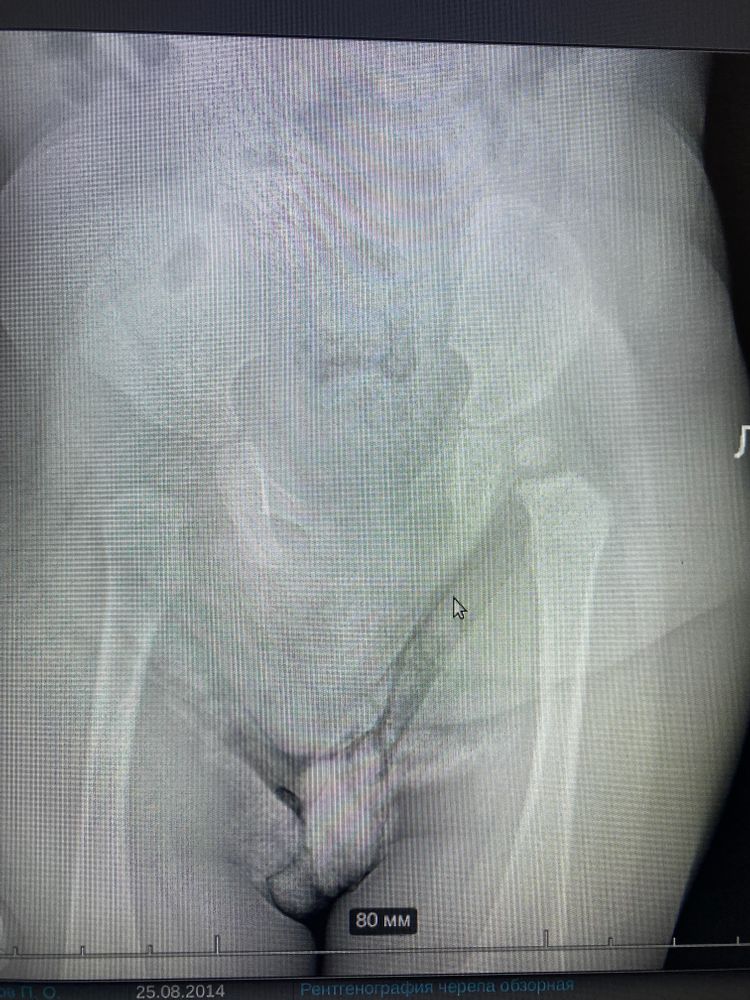

А врач что сказал? Они же там углы меряют, смотрят, окостенение. Ну визуально слева не так чётко.